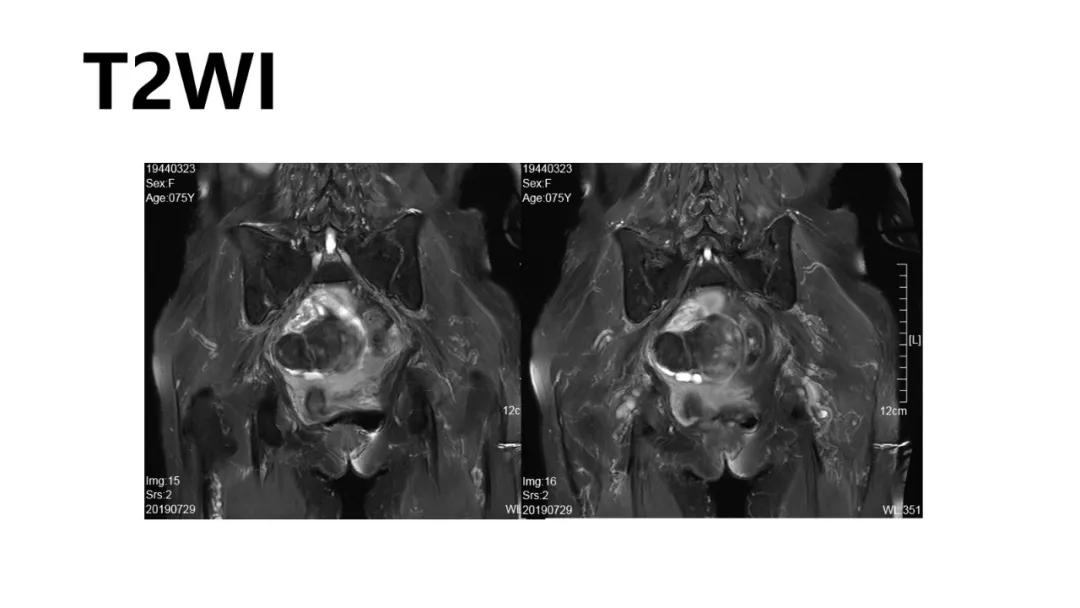

病理:左侧卵巢卵泡膜-纤维瘤